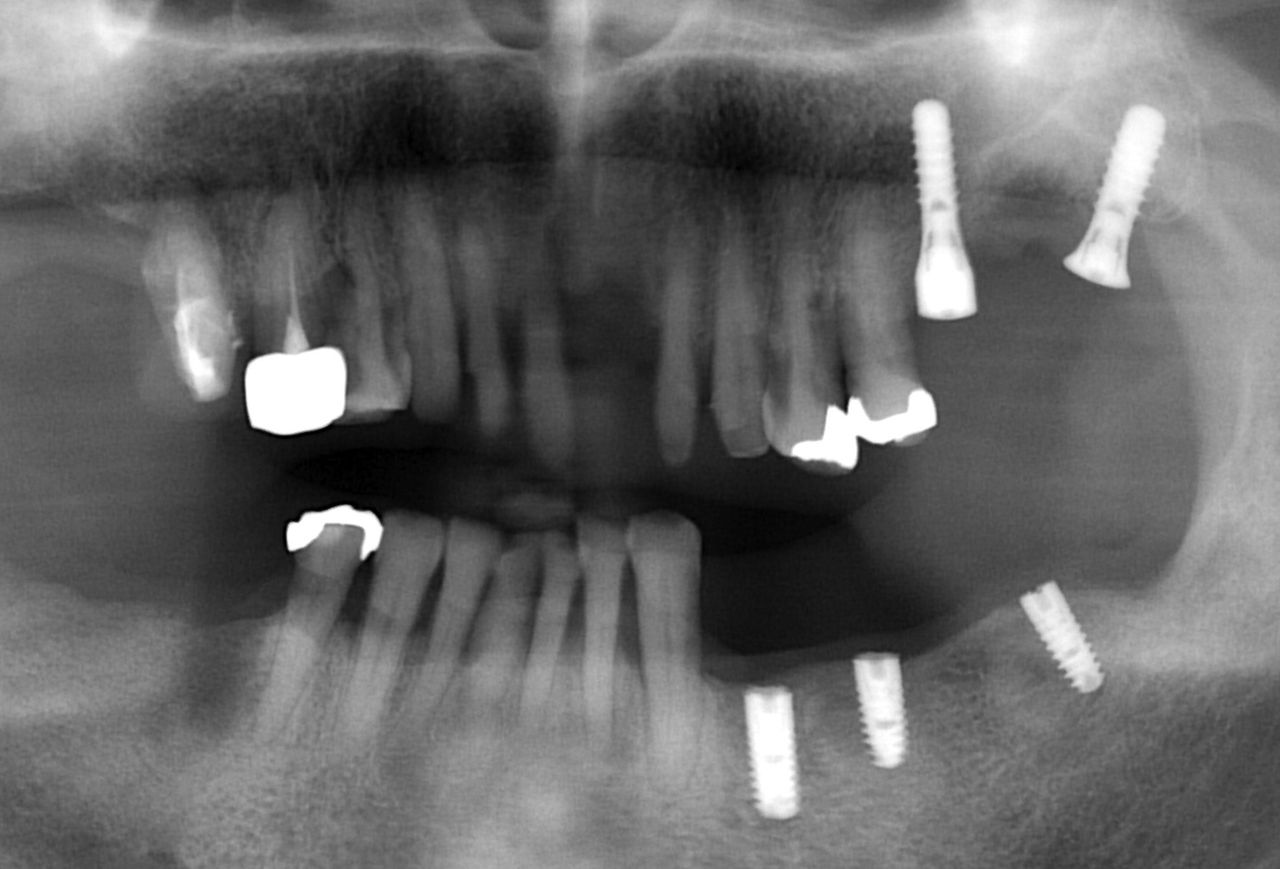

以下がインプラント治療が終了した後のレントゲンです。

最後に 今回のインプラント治療とは関係ありませんが、

この患者様は、神経がない歯が非常に多いのが問題です。

最初にも書きましたが、神経のない歯は もろく 通常の咬む力でも割れてしまうことがあります。

歯根破折 です。

今後も注意してみていかないといけません。